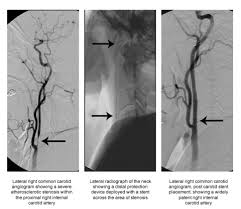

Check out the following learning materials to learn about the major arteries of. · a carotid aneurysm is an aneurysm in one of the carotid arteries which supplies the neck and head with oxygenated blood. The arteries that ultimately supply the head and neck originate from the subclavian and common carotid arteries. A blockage in one of the carotid arteries can be cleared either by endarterectomy or carotid angioplasty. A publicly available article also appearing in pubmed about anatomy, head and neck, striate arteries. The carotids reside beneath the skin on either side, and the pulse can be felt easily with your hand. Carotid artery disease occurs when fatty material called plaque builds up inside the arteries. Overview of arteries of the neck 0:16. From this trunk, several vessels arise, which go on to supply the neck. The left and right carotids, and the left and right vertebral arteries. The carotid artery is the main artery that carries blood from the heart to the brain. I also have irritable bowel syndrome and i'm wondering if it's all connected. /kəˈrɒtɪd/) are arteries that supply the head and neck with oxygenated blood;

Neck arteries can become blocked in the same way as other arteries in the body, such as the coronary arteries that supply the heart muscle.